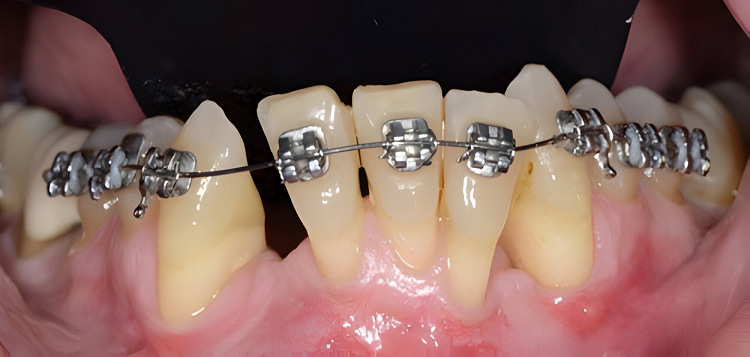

X-Matrix ứng dụng SmileStream trong việc phân tích phim và lên kế hoạch điều trị

Để khắc phục nhược điểm của công nghệ cũ, niềng răng X-Matrix ứng dụng các công nghệ hiện đại ngay từ bước thu thập dữ liệu để đảm bảo độ chính xác tuyệt đối:

- Scan dấu răng bằng máy iTero Element 5D đại để khảo sát tương quan răng và mô mềm, xác định các sai lệch về răng và khớp cắn chính xác tới từng micromet.

- Phần mềm Autolign: đo đạc và mô phỏng hình dạng cung răng trong 3 chiều không gian, cá nhân hóa lựa chọn dây cung phù hợp nhất với tình trạng răng, lựa chọn hướng đặt mắc cài giúp răng di chuyển đúng vị trí 1 cách chuẩn xác, mô phỏng kết quả niềng răng chính xác tới 99,9%.